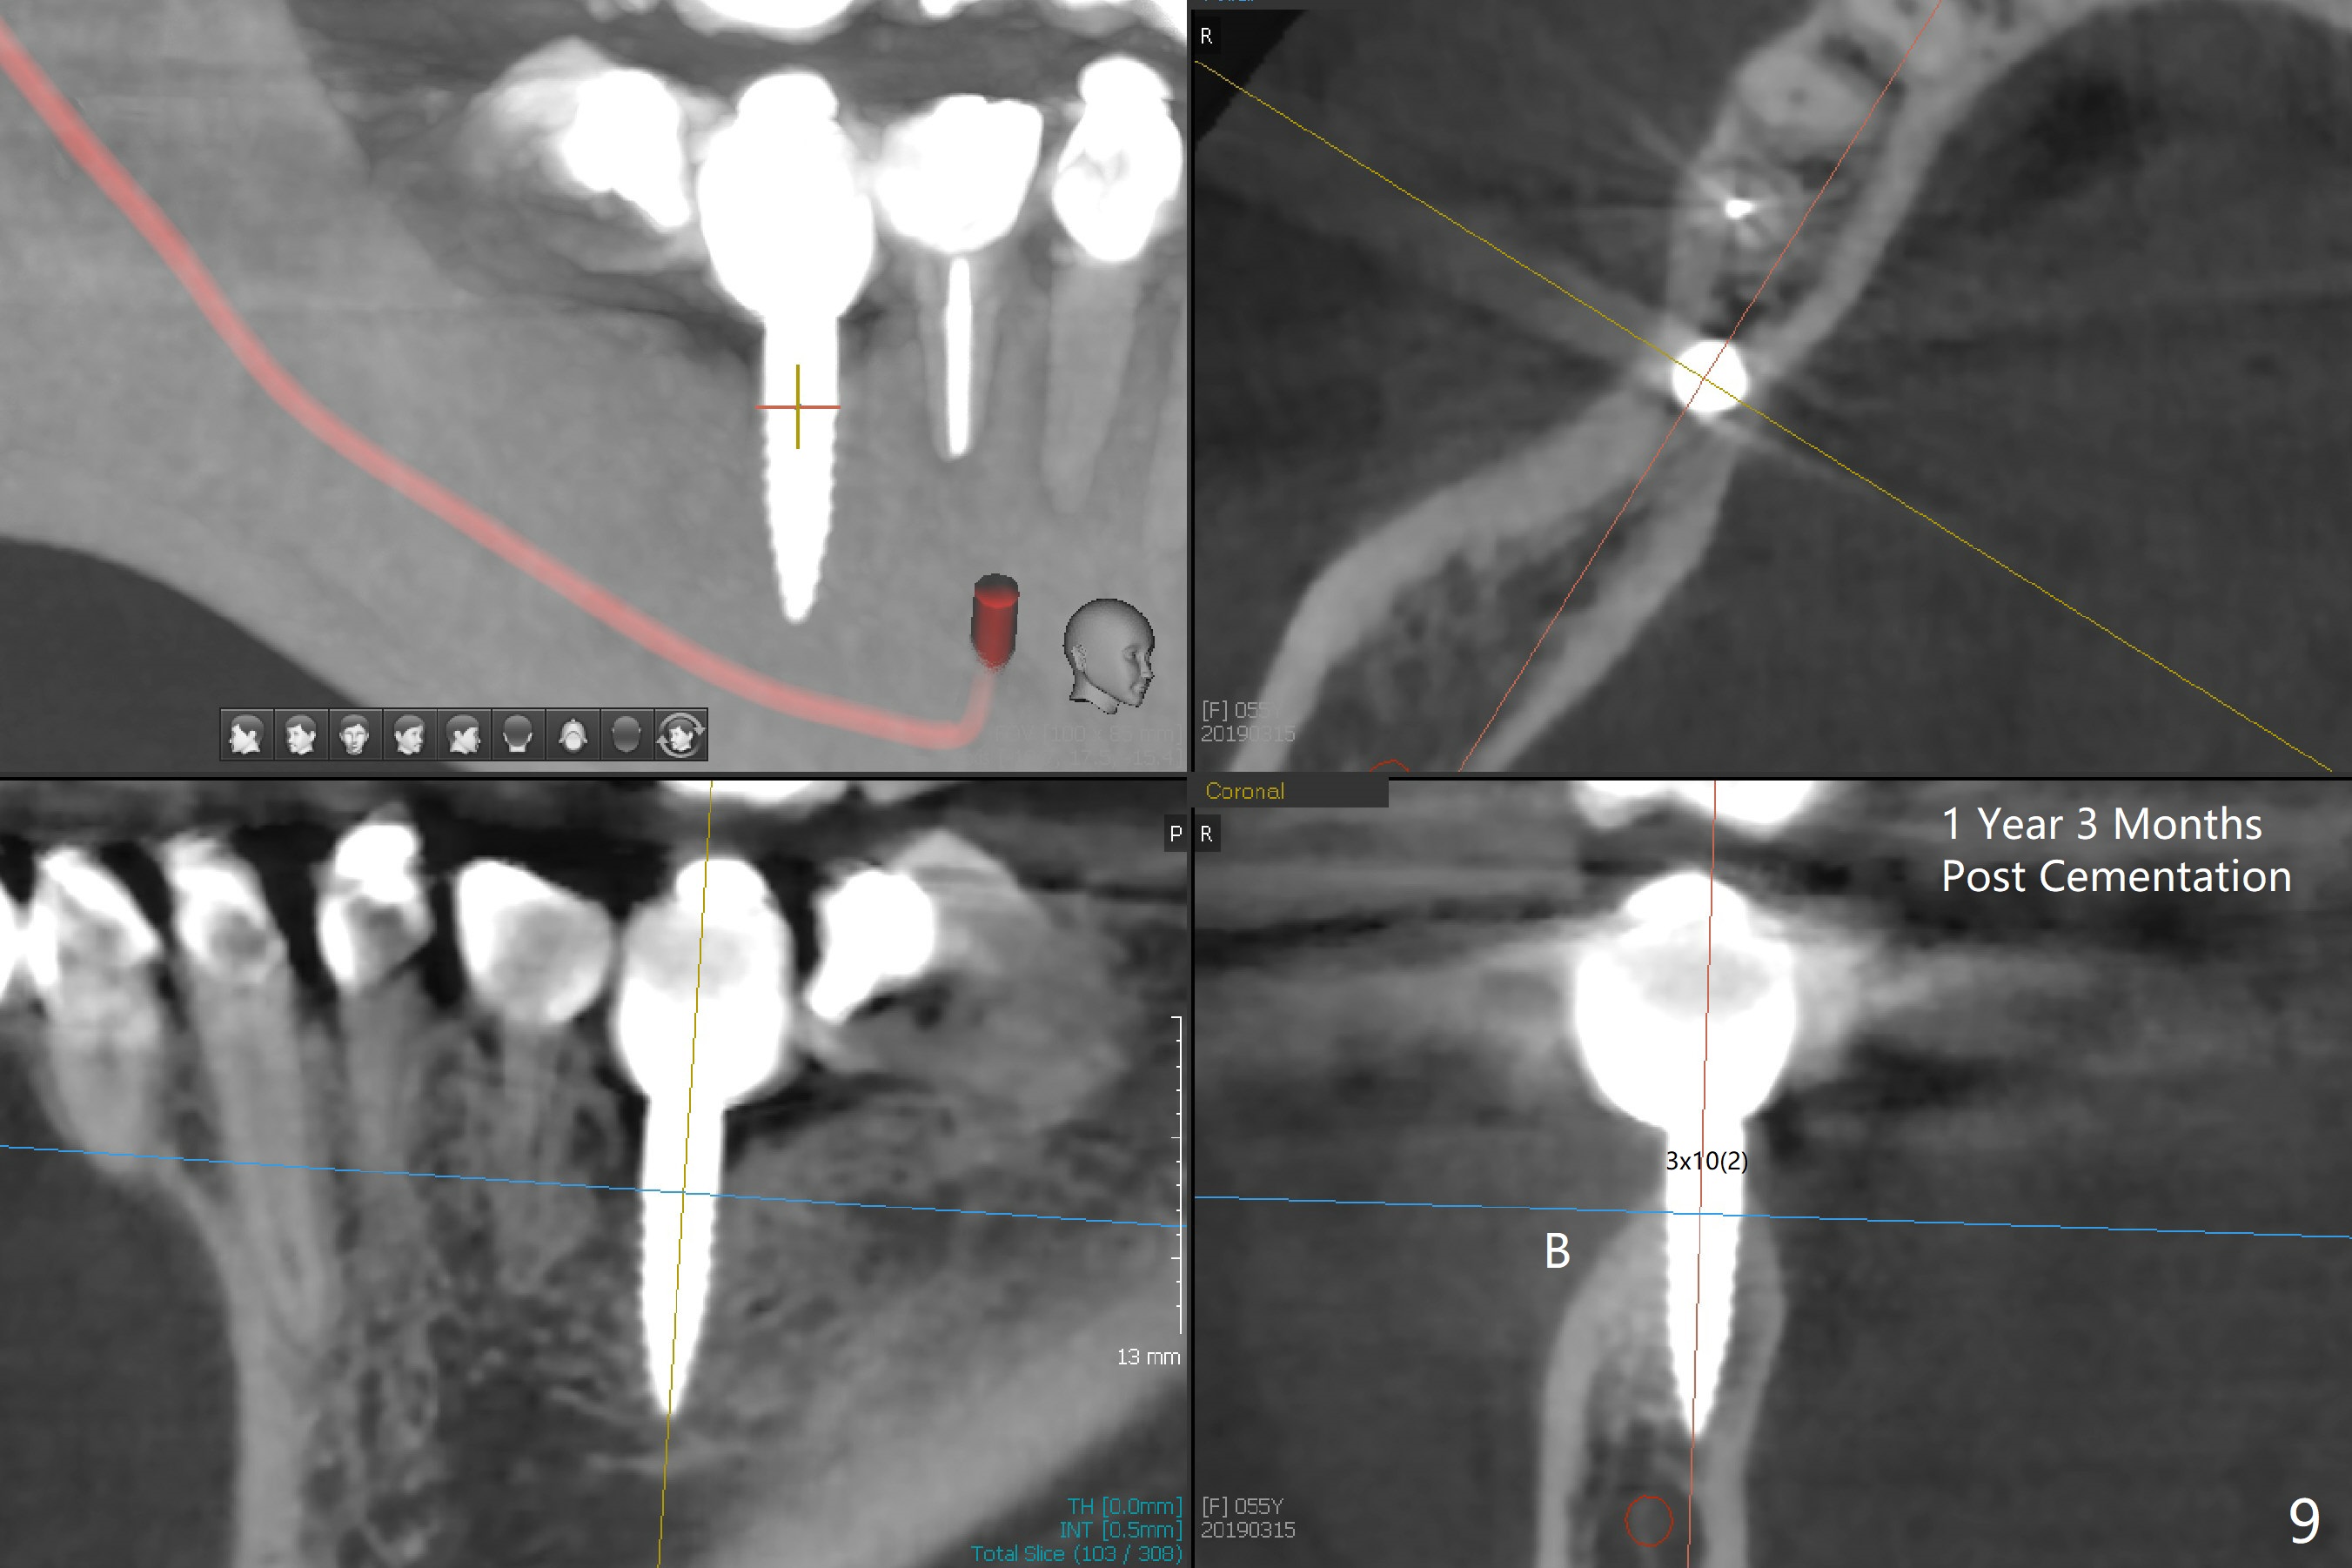

Incision reveals a narrow ridge and a narrow mesiodistal space at #30 (Fig.1).  It seems that a 1-piece implant is indicated.  Due to limited mouth opening, a 1.2 mm drill is unstable in place after use for 10 mm; instead a 1.5 mm drill is able to be inserted for 8 mm (Fig.2).  A 3x10(2) mm 1-piece dummy implant is placed with 40 Ncm at an apparently acceptable level (Fig.3 >).  Clinically a few threads are exposed buccally.  When a definitive implant with the same dimension is inserted with 45 Ncm, it looks seated too deep (Fig.4,5).  The latter is noted after suturing.  The implant is backed up for a few turns so that the length of the abutment appears a little more reasonable.  Introspectively, a 4 mm cuff should have been used after ridge reduction.  Although there is no bone loss 4 months postop (Fig.6), the abutment margin (Fig.7 arrow) is subgingival (red dashed line: gingival margin).  Diode laser is used for gingivectomy prior to impression.  The bone density around the implant increases 11 months post cementation (Fig.8 *), probably related to recurrent #18 infection.  The patient uses floss after meal.